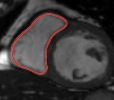

The problem above is a generalization of Horn & Schunck optical flow. Note that solving for the Horn & Schunck optical flow within each region separately does not lead to motions such that at the interface, they have equal normal components (see Figure 1), whereas the solution of (5) to be presented in subsequent sections does. Note that computing Horn & Schunck optical flow in each region requires boundary conditions (and typically they are chosen to be Neumann boundary conditions: and on ). Note that replacing these boundary conditions with the boundary constraint (6) does not specify a unique solution. Also, while Horn & Schunck optical flow computed on the whole domain naturally gives a globally smooth motion, which by default satisfies matching normals at the interface, this is not natural for the ventricles / myocardium, where different motions exist in the regions (see Figure 2), and the motions should not be smoothed across the regions.

![]() |

| image + boundary | next image | within region optical flow | our method |